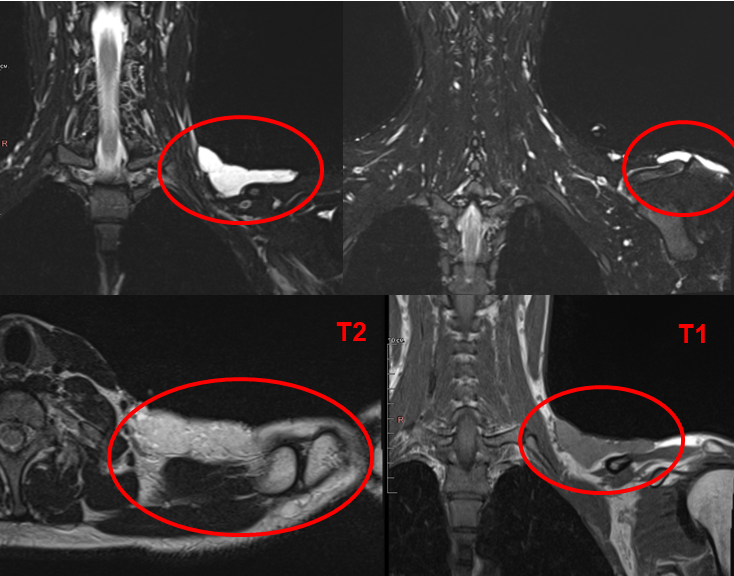

Молодой человек 22 лет обратился с жалобами на периодические боли в области шеи и образование, которое он ощущал под кожей.

При обследовании с помощью магнитно-резонансной томографии врачи-рентгенологи Центра Илизарова выявили жидкостное образование неоднородной структуры в надключичной области.

По предварительному заключению экспертов рентгеновского отделения Центра Илизарова, у пациента гемангиома или лимфотическая мальформация.